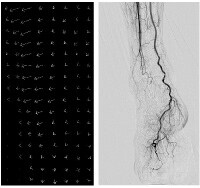

Real-time whole peripheral observation, "SCORE Chase"

Long-view whole peripheral image is automatically stitched and displayed right after acquiring Shimadzu original MASK less DSA named "SCORE RSM". Under combination with SMART Table, it is much easier to approach to region of interest.